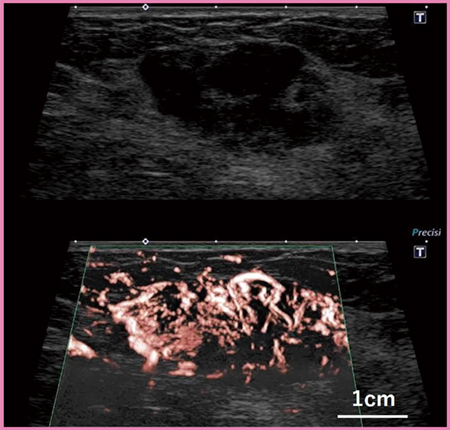

PLI-1205BXは4.0〜18.2MHzと広帯域であり,乳腺検査に十分な視野深度と浅〜深部まで均一な高画質を実現している。また,PLI-2004BX(8.8〜24MHz)は,乳腺領域の通常および精密検査に対応するため,約4cmの視野幅と実用に堪える視野深度を確保している。その上で,24MHzという高周波により,今までにない高画質画像を提供する。これらのプローブのBモード画像では,例えば腫瘤の形状や境界だけでなく,内部構造まで詳細に観察することができる(図1)。

図1 超高周波プローブ「PLI-2004BX」による乳腺のBモード画像

(画像提供:名古屋医療センター・森田孝子先生)